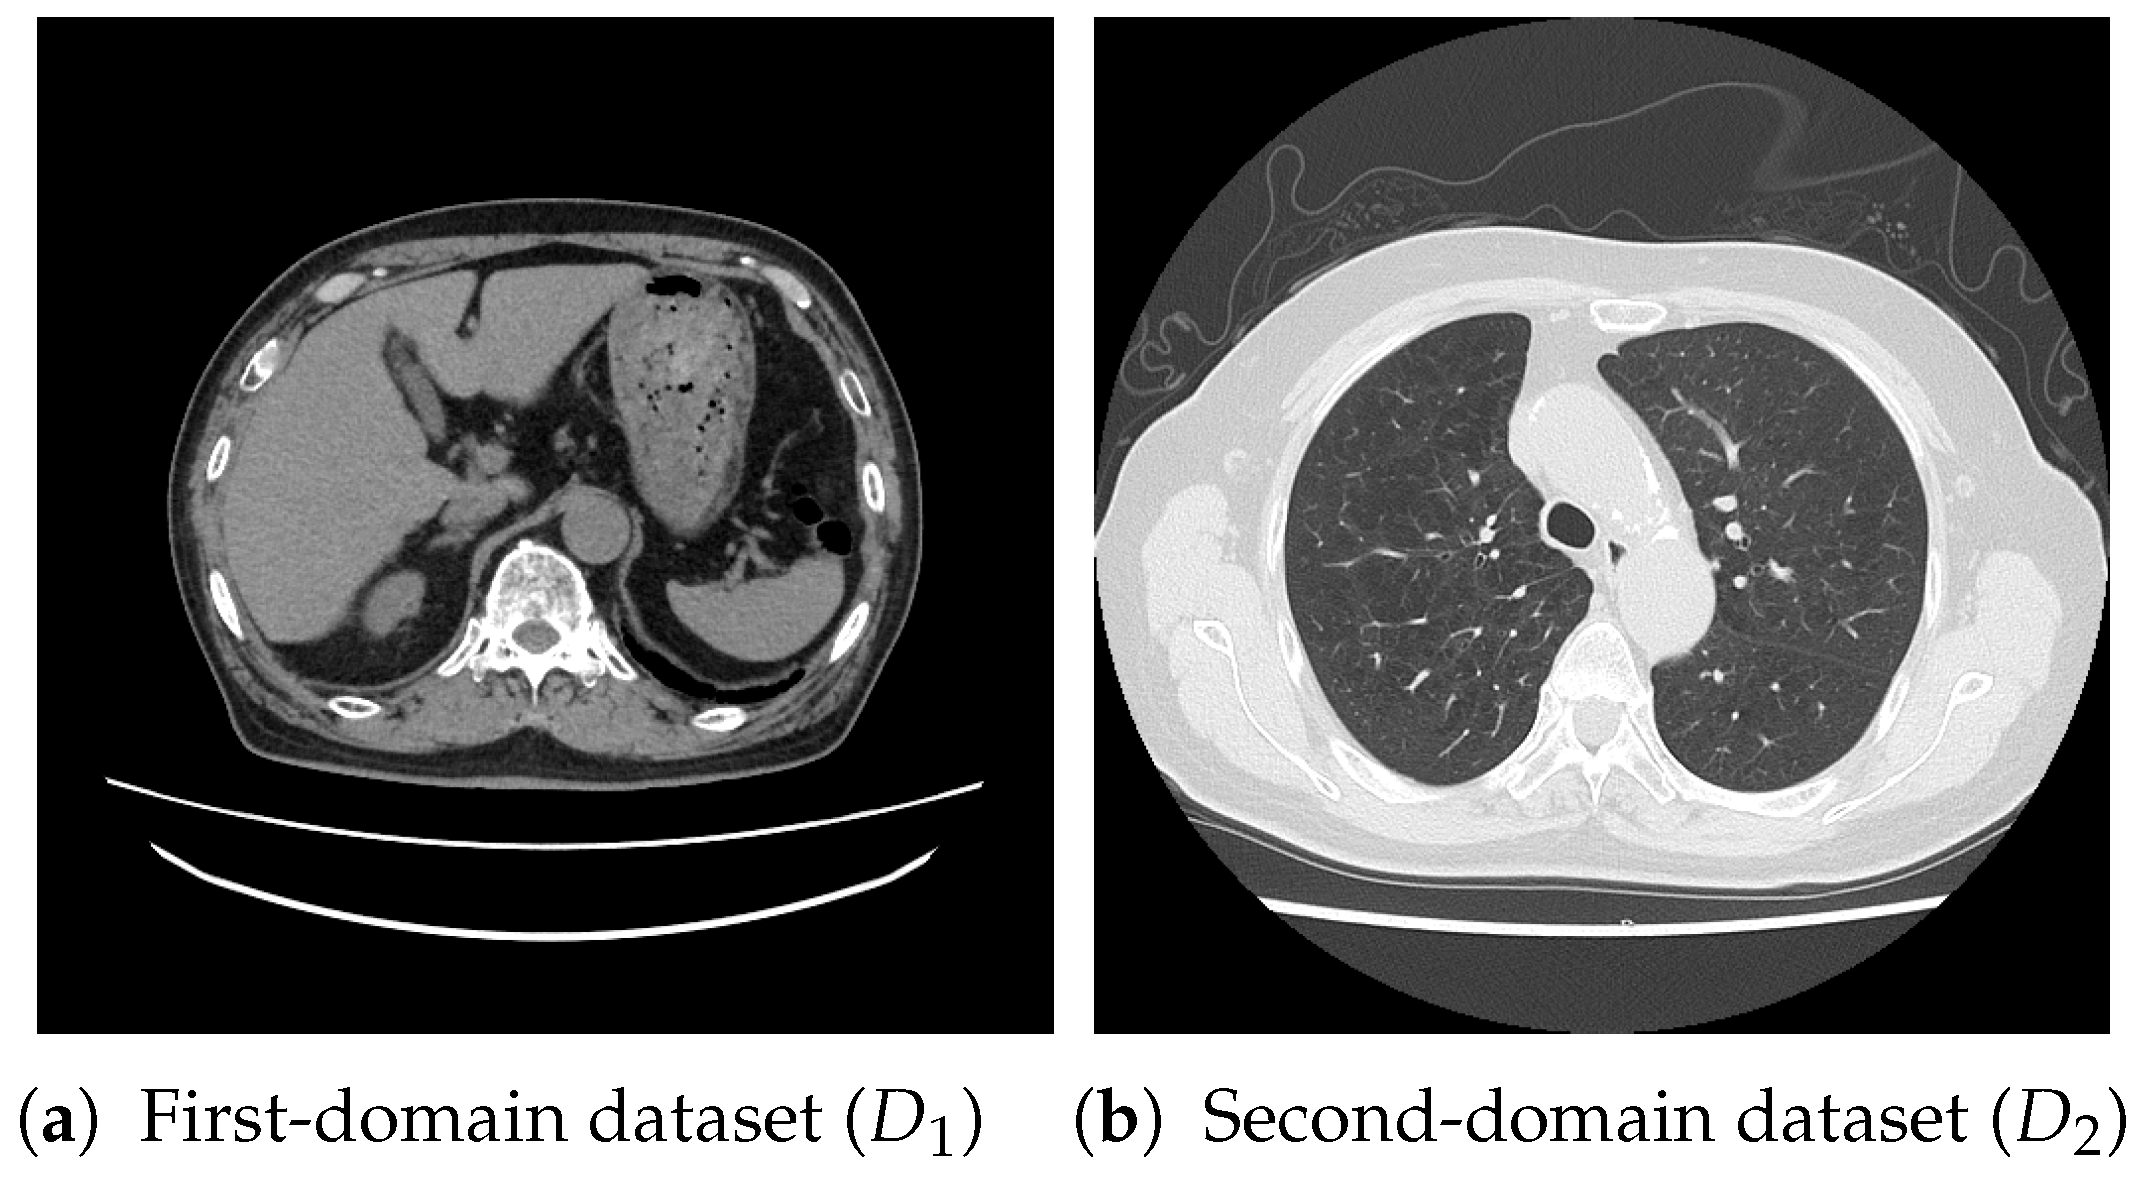

4.1. Datasets and Settings